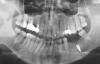

Geravital Опубликовано 21 октября, 2010 Поделиться Опубликовано 21 октября, 2010 (изменено) Начал решать проблему жевательного комплекса.Врач убедил поставить мне только один имплант, а мост ставить на имплант и здоровый зуб(4-ка). Т.к. я не разбираюсь, то согласился на такую конфигурацию. Имплант вкрутили(см..фото). Теперь очередь за мостом. Но закрались сомнения.Теперь многие стоматологи не рекомедуют депульпировать здоровый зуб. Советуют добавить импланты, а на них уже ставить мост. Выскажите, какое решение бы применили вы? Очень интересно получить общее мнение сообщества и на этом попробовать приянть решение Кроме всего я хотел бы услышать ответы на следующие вопросы:1. Стоит ли трогать здоровый зуб - депульпировать и ставить на него мост?2. Если ставить мост на один имплант и зуб - будет ли это прочно и в среднем сколько такая конструкция будет держаться?3. Можно ли вкрутить еще 1 или 2 импланта по бокам существующего и ставить мост на 2, на 3 импланта?4. Насколько прочная будет конструкция из 2х имплантов Стоматологи говорят, что один имплант выдерживает нагрузке одного зуба. В то время, как один зуб имеет запас прочности и может выдержать нагрузку 2х зубов. Поэтому я так понимаю, надо на место промежутка вкручивать всего 3 импланта, чтобы все хорошо держалось Изменено 21 октября, 2010 пользователем Geravital Ссылка на комментарий

Bier Опубликовано 23 октября, 2010 Поделиться Опубликовано 23 октября, 2010 этот имплантат как-то вообще бестолку стоит. Поставлен слишком глубоко, да и непонятно зачем посередине, во первых при такой глубокой постановке его не отпротезировать, во вторых соединять зубы с имплантатами нельзя. Если еще не прижился - удаляйте. Если прижился - оставьте как есть, поставьте два рядом и сделайте на них мост. Ссылка на комментарий

Aldo Rain Опубликовано 23 октября, 2010 Поделиться Опубликовано 23 октября, 2010 просто снаряд какой-то в челюсти... Ссылка на комментарий